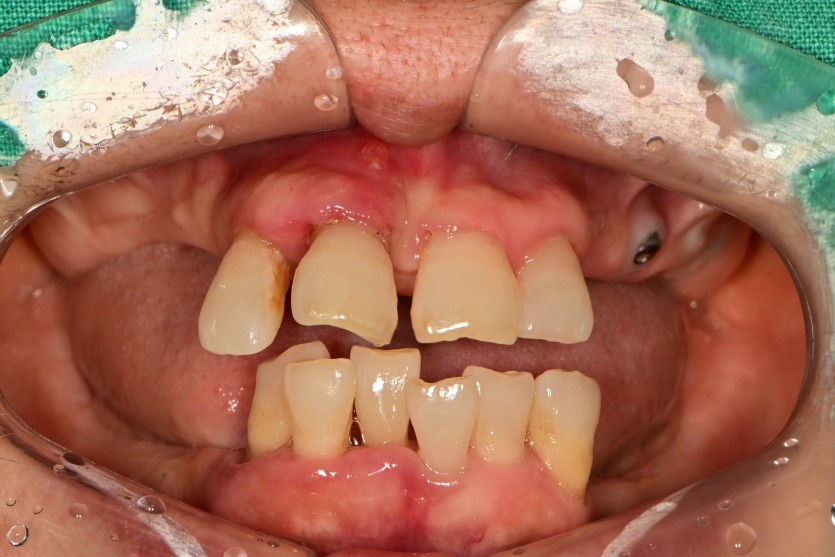

만 58세 전체 임플란트 증례입니다.

18개의 임플란트로 완성하였습니다.